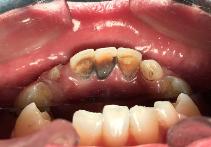

8岁孩子口内外源性染色

牙齿分为内源性和外源性,今天着重介绍外源性染色。外源性牙齿染色的原因很多,总结起来有以下的原因:日常饮食黑色素较多的食物(最常见),长期服用颜色较深的中药,口腔内产黑色素细菌活跃等。染色一般位于牙齿的唇颊侧,部分严重的患儿可有舌侧及咬合面的染色。